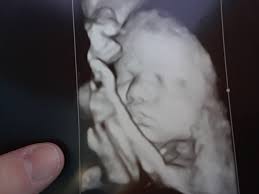

If the 2D ultrasound does not demonstrate two nasal bones then 3D ultasound may be useful. An ultrasound scan There is no risk to the baby from either of these procedures. October 15 2018 Shane Dale According to the National Down Syndrome Society NDSS during the normal fertilization of a womans egg by a mans sperm the resulting nucleus of each cell in a fetus contains 23 pairs of chromosomes half of which are inherited from each parent.

For this reason 3D ultrasound reconstruction of the nasal bone and other facial bones is useful. At this stage the babys legs arms fingers and toes should be fully formed. Mothers should not be encouraged to have an ultrasound called a.

Of the many defects 3D 4D ultrasound has been useful in evaluating the skeletal and cardiovascular systems in fetuses with this condition. But keeping tabs on your babys growth can be a good thing and knowledge is power. By combining the results of the two parts of the test it is possible to identify if a pregnant woman is at increased risk of having a baby with Down syndrome.